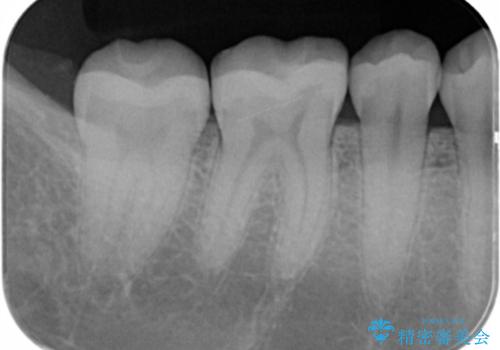

写真でもレントゲン画像でも確認できるように、段差がなく適合の良い詰め物を装着することができました。